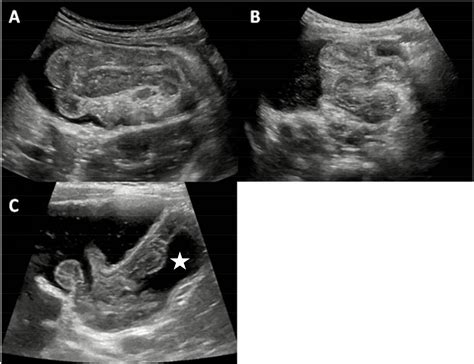

When performing an ultrasound to detect intussusception on ultrasound, radiologists look for specific signs that indicate the presence of intussusception. These signs include:

• Target or doughnut sign: This appears as concentric rings of alternating hypoechoic and hyperechoic layers, representing the invaginated intestine.

• Pseudo-kidney sign: This sign is seen when the intussusceptum (the invaginated segment) appears as a hypoechoic mass with a hyperechoic rim, resembling a kidney.

• Crescent-in-doughnut sign: This sign is observed when there is a crescent-shaped hypoechoic area within the doughnut sign, indicating the presence of mesenteric fat.

• Non-surgical Reduction: This involves the use of air or contrast enema to reduce the intussusception. Ultrasound guidance can be used to monitor the procedure and assess its success.